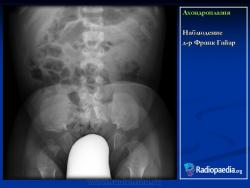

Наблюдение д-ра Франк Гайар

Характерными признаками гетерозиготной ахондроплазии являются укорочение конечностей, поясничный лордоз, короткие пальцы, макроцефалия с выступающим лбом и запавшей переносицей. Трубчатые кости, как правило, сохраняют правильную форму. Их деформация встречается не более чем в 25-30% наблюдений. Грудная клетка и живот не отстают от нормативных для срока значений.